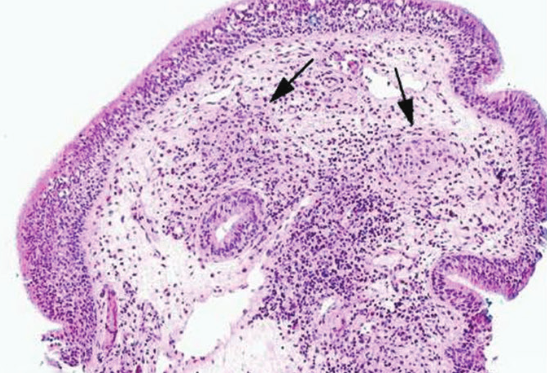

Renal allograft recipients are at greater risk of developing tuberculosis than the general population. A woman with a kidney transplant was admitted to our emergency department with high temperature, dysphonia, odynophagia, and asthenia. The final diagnosis was laryngeal tuberculosis. Multidisciplinary collaboration enabled accurate diagnosis and successful treatment. Laryngeal tuberculosis should be considered in renal allograft recipients with hoarseness. A more rapid diagnosis of tuberculosis in renal transplant recipients is desirable when the site involved, such as the larynx, exhibits specific manifestations and the patient exhibits specific symptoms. In these cases, prognosis is excellent, and with adequate treatment a complete recovery is often achieved.